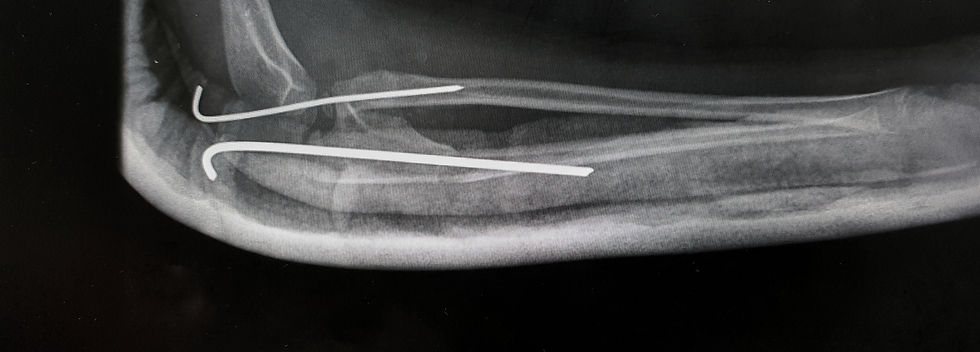

O diagnóstico é geralmente confirmado por meio de radiografias, permitindo que possamos avaliar a extensão da fratura e planejar o tratamento adequado, que pode variar de acordo com a gravidade da fratura. Em casos menos graves, opta-se por imobilização com uma tala para permitir a cicatrização adequada. Em fraturas mais complexas, pode ser necessário recorrer à intervenção cirúrgica para realinhar e fixar a cabeça do rádio.